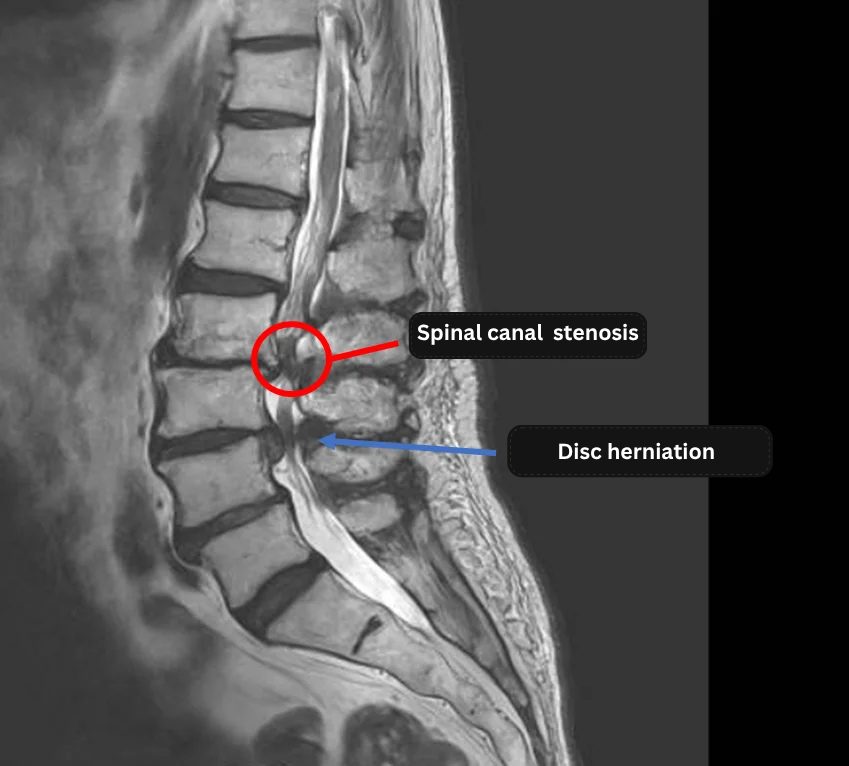

- L1/2, L2/3, L3/4, L4/5, L5/S1: Disc degeneration

- L3/4: Disc herniation

- L3/4: Spinal canal stenosis

The above findings were also observed on the imaging.

・The disc herniation at L3/4, in correlation with clinical symptoms, is highly likely the primary cause of the patient’s condition.